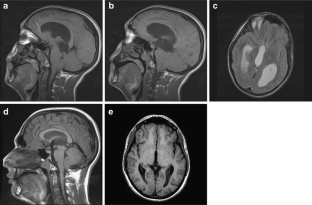

The sylvian aqueduct is the most common site of intraventricular blockage of the cerebro-spinal fluid. Clinical aspects, neuroradiological appearance, and treatment of hydrocephalus secondary to aqueductal stenosis are specific.

The correct interpretation of the modern neuroradiologic techniques may help in selecting adequate treatment between the two main options (third ventriculostomy or shunting). In the last decades, endoscopic third ventriculostomy has become the first-line treatment of aqueductal stenosis; however, some issues, such as the cause of failures in well selected patients, long-term outcome in infant treated with ETV, and effect of persistent ventriculomegaly on neuropsychological developmental, remain unanswered.